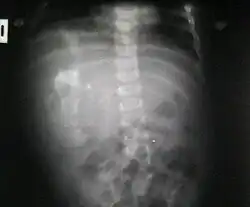

Fetus in fetu (łac. foetus in foeto, fœtus in fœtu; dosłownie "płód w płodzie") – rzadka anomalia, polegająca na obecności zwapniałej, płodokształtnej masy w obrębie jamy ciała noworodka lub niemowlęcia. Fetus in fetu powstaje wskutek nierównomiernego rozdziału totipotencjalnych komórek blastocysty, i obecności inkluzji małej grupki tych komórek w obrębie bardziej dojrzałego zarodka. Jest to więc postać monozygotycznej dwuowodniowej ciąży wielopłodowej[2]. Jest to rzadka malformacja, pod wieloma względami zbliżona do zaotrzewnowego potworniaka, ale różniąca się ukształtowaniem patologicznej masy i jej metameryczną segmentacją w obrębie osi kręgosłupa. Masa guza zazwyczaj jest otorebkowana i posiada własną szypułę naczyniową[3].